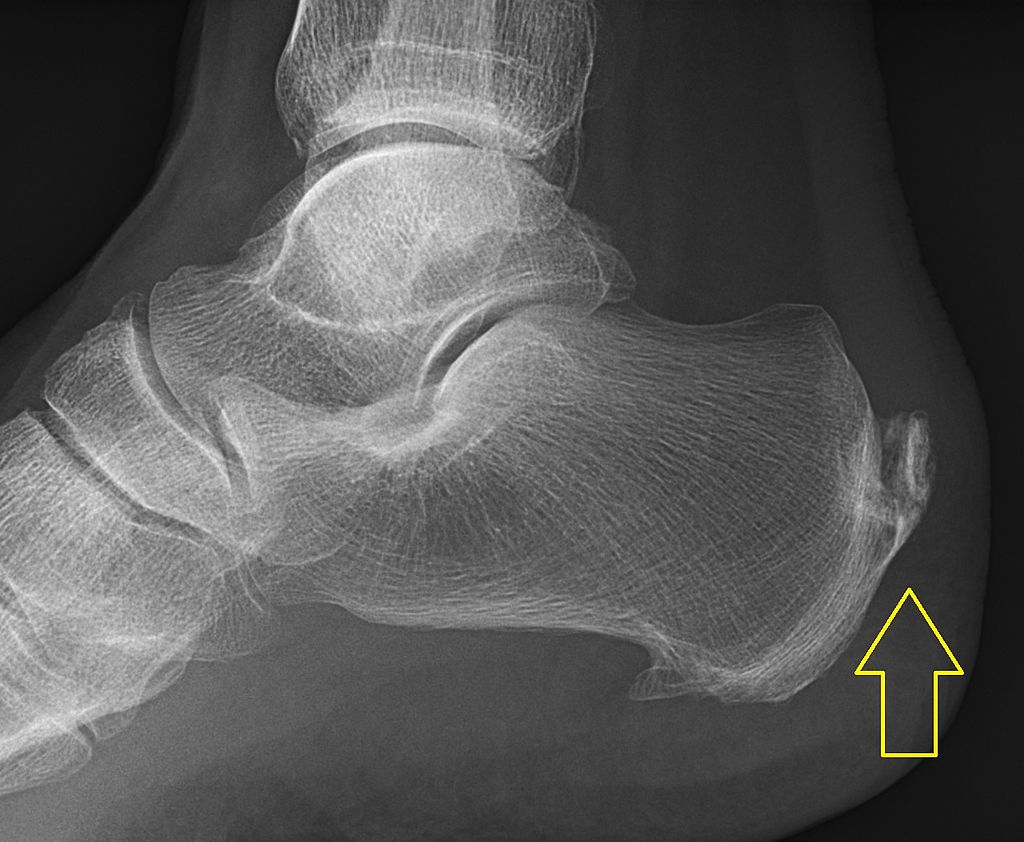

Przyczyna 7: Dna moczanowa

Przyczyną tej choroby jest nieprawidłowy poziom kwasu moczowego we krwi który krystalizuje w tkankach. Choroba ma charakter przewlekły i często prowadzi do nawracających stanów zapalnych. Często zaczyna się od okolicy dużego palca u stopy